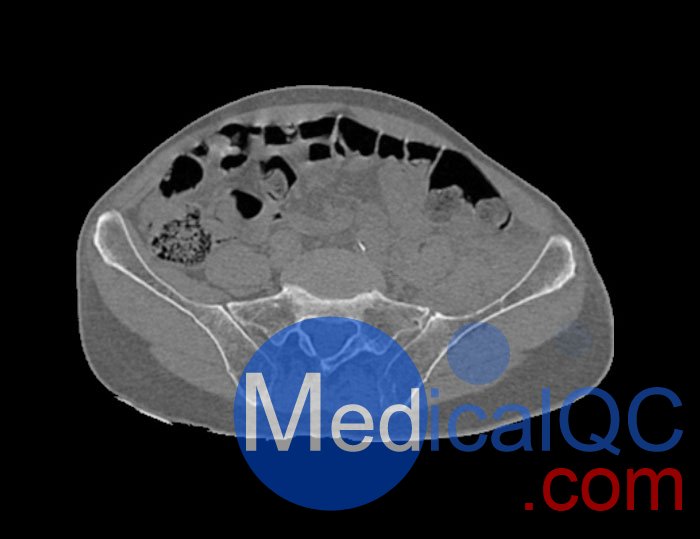

左側(cè)股骨頸移位骨折。

WEK54-01股骨頸骨折骨盆模型,WEK54-01骨盆模體提供了對(duì)軟組織和骨組織的詳細(xì)而逼真的模擬??障吨刑畛渲s-160HU的纖維素-聚合物復(fù)合材料。

骨骼和軟組織的逼真模擬。